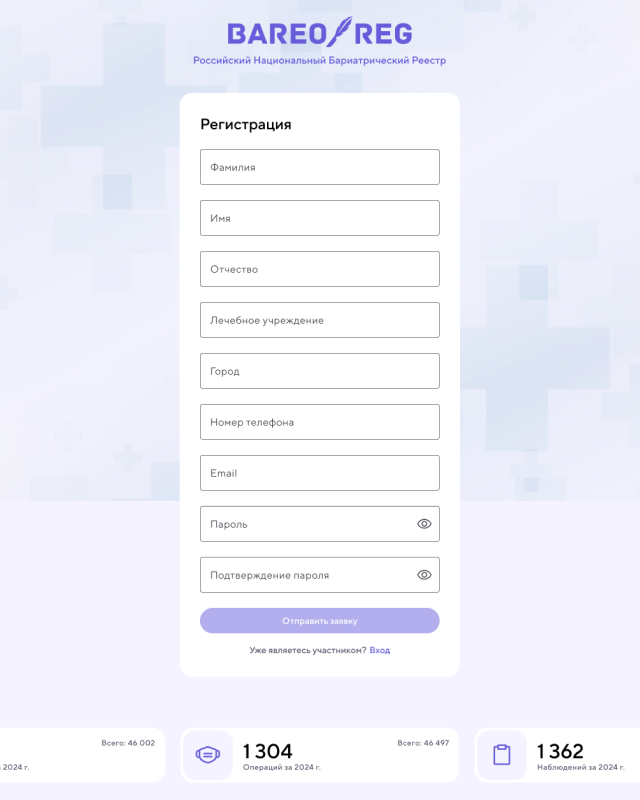

CRM Приложение [ 2022 ]

Работал над CRM-приложением для хирургической клиники по снижению лишнего веса, разработанным с использованием Pug, Vanilla.js и CSS. Приложение предназначено для ведения и учета пациентов, управления операциями и отслеживания результатов лечения.

В рамках проекта реализованы: авторизация и роли пользователей, создание и ведение карт пациентов, продвинутая фильтрация по различным параметрам, а также большие формы для создания операций и наблюдения за пациентами. Для визуализации результатов лечения использовались Chart.js, позволяя наглядно отображать статистику и эффективность применяемых методов.

Я работал над архитектурой интерфейса, реализацией ключевых функций, обеспечением удобного и логичного взаимодействия с данными, а также над оптимизацией форм и графиков для комфортной работы медицинского персонала. Приложение получилось функциональным, наглядным и удобным инструментом для управления пациентами и анализа результатов клиники.